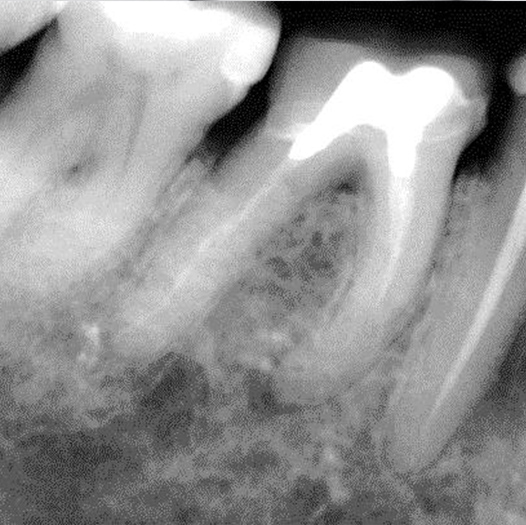

After

After Root Canal treatment